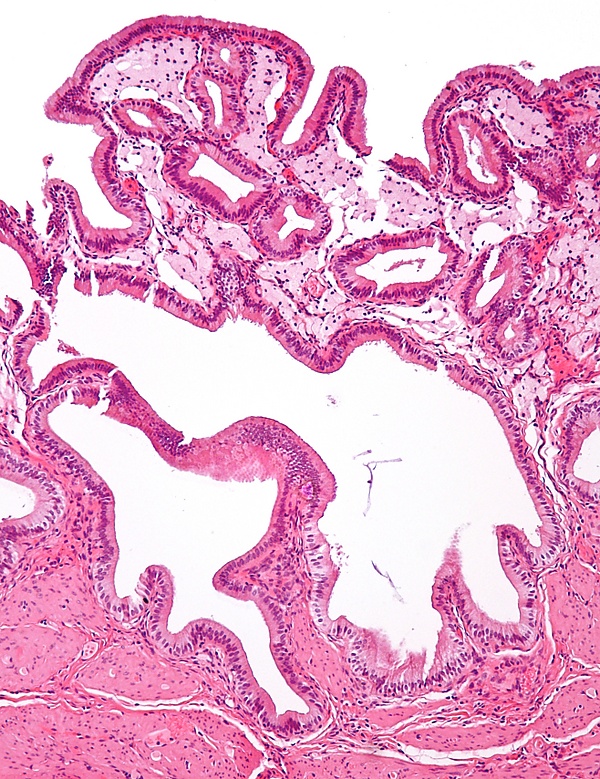

Механизм развития холестероза желчного пузыря исследован достаточно хорошо. Липиды, откладывающиеся в стенке органа, поступают из видоизменённых липопротеинов низкой плотности, отличающихся изменениями в структуре аполипопротеинов. Вследствие этих преобразований липопротеины получают способность связываться с рецепторами макрофагов. Подвергшиеся модификации липопротеины легче проникают внутрь стенки желчного пузыря, поглощаются макрофагами и образуют пенистые клетки. Внешне скопление пенистых клеток на верхушке ворсин выглядит как жёлтые пятна на внутренней оболочке желчного пузыря[5].

Проводится гистологическое исследование желчного пузыря после холецистэктомии. При котором обнаруживают пенистые клетки или отдельные их скопления в слизистой оболочке и подслизистом слое желчного пузыря, а также признаки дистрофии эпителия[5].